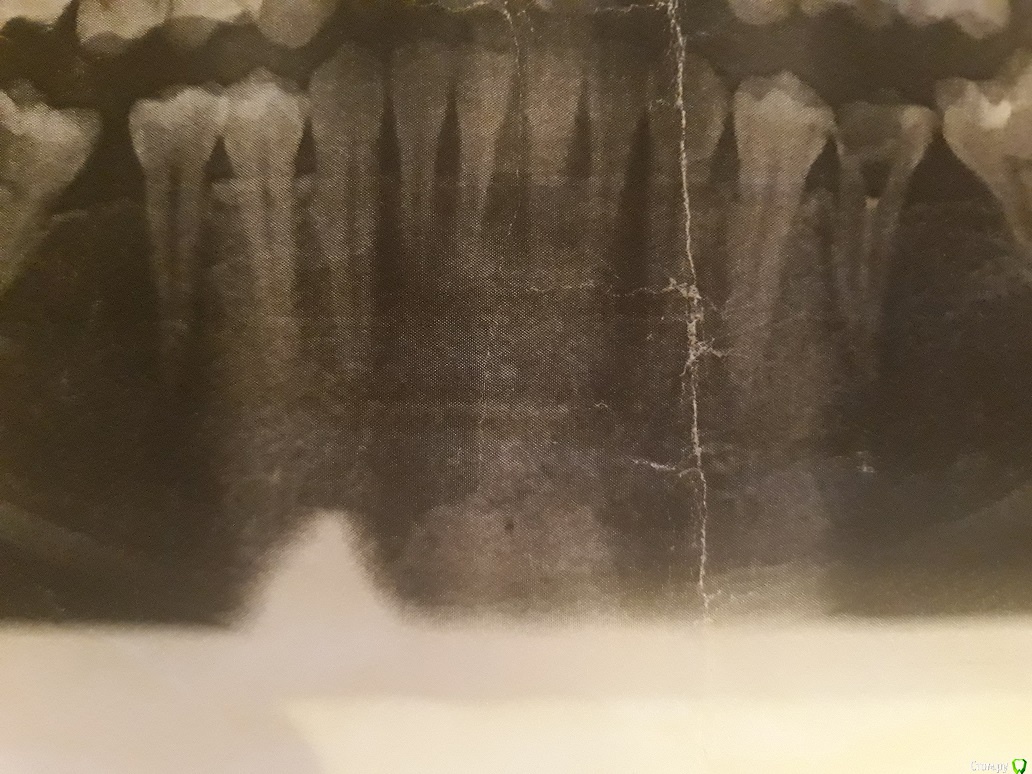

St. Опубликовано 4 августа, 2019 Поделиться Опубликовано 4 августа, 2019 Добрый день. Проблема не в том что сняли зубные отложения, а в том что кость ушла от воспаленной десны и когда воспаление десны после гигиены прошло десна как бы "села в обьеме".Покажите фото зубов и панорамный снимок желательно.от этого будут зависеть рекомендации Ссылка на комментарий

nata* Опубликовано 4 августа, 2019 Автор Поделиться Опубликовано 4 августа, 2019 Спасибо за ответ! Вот фото Ссылка на комментарий

St. Опубликовано 5 августа, 2019 Поделиться Опубликовано 5 августа, 2019 в вашем случае кость ушла вниз уже достаточно сильно, оголив корни.Вам нужно обязательно и регулярно делать профессиональную чистку и тщательно чистить дома. Так можно будет стабилизировать этот процесс, иначе кость будет уходить и дальше, и зубы в будущем начнут шататься. Вернуть десну до исходного уровня увы не получится.. Ссылка на комментарий